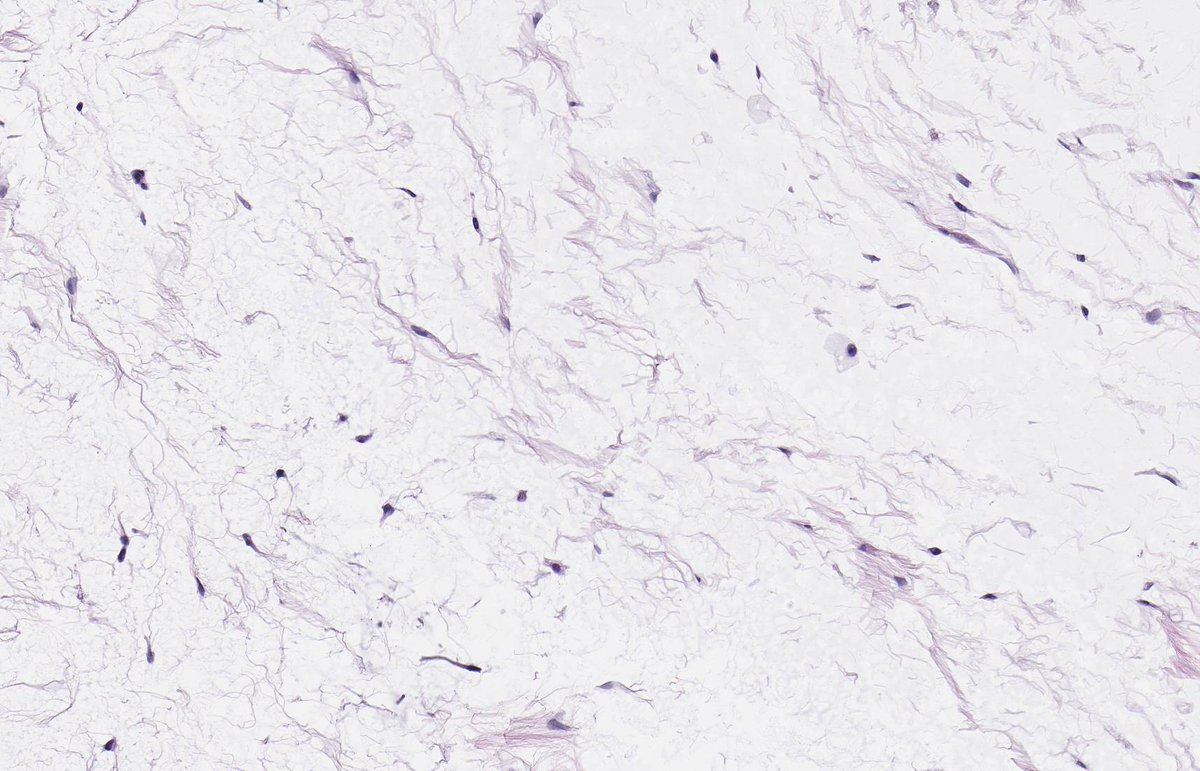

MASSIVE LOCALIZED LYMPHOEDEMA. NB: lobules of mature adipose tissue; expanded interlobular septa; spindle-stellate cells with mild atypia and prominent myxoid background; ectatic lymphatic spaces; MDM2 non-amp; typically occurs in context of morbid obesity (PMID: 9777990).